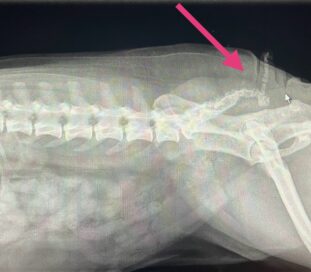

Før operationen tages et røntgenbillede af bagparten, så halehvirvlernes placering kan vurderes.

Der lægges et ovalt snit rundt omkring halens tilhæftning på rumpen. Ud fra røntgenbillederne vurderes halehvirvlernes udformning og ud fra dette besluttes, hvor snittet skal lægges. Det er stort set aldrig muligt at bevare noget af halen.

Huden sys sammen, og der tages et nyt røntgenbillede af halen.